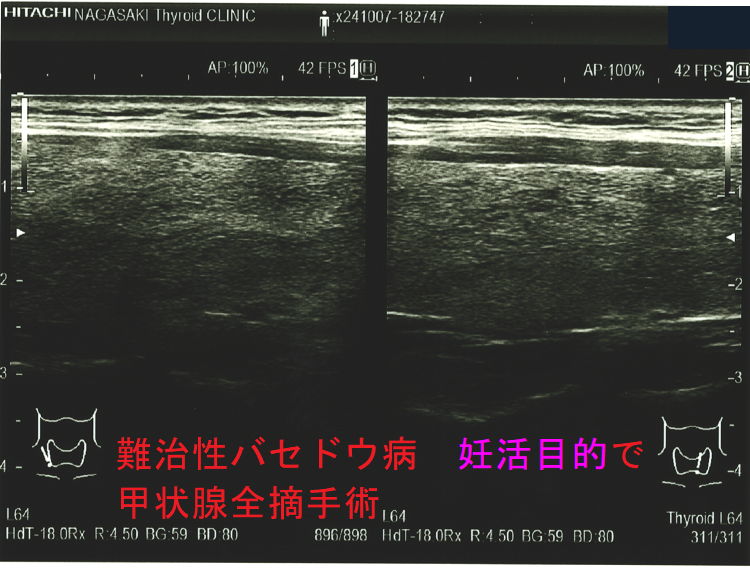

妊娠中、抗甲状腺薬(メルカゾール、プロパジール、チウラジール)+ヨウ化カリウム(KI)でもバセドウ病/甲状腺機能亢進症をコントロールできない時は、もはや妊娠2期(中期)の甲状腺全摘手術になります。[GUIDANCE TO THE MATERNAL, FETAL AND NEONATAL MANAGEMENT OF RESISTANCE GRAVE'S DISEASE IN PREGNANCY. Acta Endocrinol (Buchar). 2021 Oct-Dec;17(4):517-520.]

甲状腺全摘手術すれば母体の甲状腺機能は安定しますが、

- TSHレセプター抗体(TRAb)は急に下がらないため、妊娠20週以降に胎児の甲状腺を刺激して胎児バセドウ病、出生後の新生児バセドウ病の発症を免れません。

- 妊娠3期(後期)の手術だと、母体の甲状腺ホルモンが胎児の脳下垂体にTSH(甲状腺刺激ホルモン)分泌抑制を掛けたままでの出生になり、新生児一過性中枢性甲状腺機能低下症を引きおこす可能性があります。

妊娠中、抗甲状腺薬(メルカゾール、プロパジール、チウラジール)が副作用で使用できなくなった時は、妊娠2期(中期)に甲状腺全摘手術になります。妊娠1期(前期)に使用できなくなった時は、2期(中期)までヨウ化カリウム(KI)で持たせます。妊娠3期(後期)に使用できなくなった時は、出産後までヨウ化カリウム(KI)で持たせます。(第54回 日本甲状腺学会 P199 抗甲状腺薬の副作用のため手術療法を行い出産に至ったバセドウ病合併妊娠の一例)[Obstet Gynecol. 2013 Aug;122(2 Pt 2):490-492.][Korean J Intern Med. 2005 Dec;20(4):335-8.]